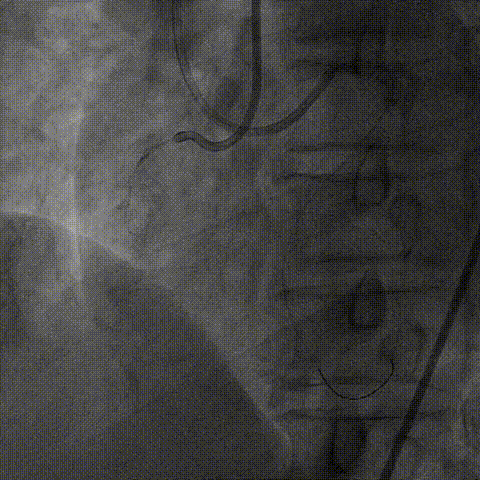

1、2.0mm顺应性球囊预扩后,Telescope™支撑下火山血管内超声(头端直径较大)无法通过,操作过程中右冠系统脱出,重新放置右冠指引管后在逆向导丝指引下正向导丝再次通过病变至右冠远端。

2、换用2.75非顺应性球囊在Telescope™支撑下扩张闭塞段并引导Telescope™通过闭塞段后完成血管内超声检查。

血管内超声:

导丝远端位于血管真腔,闭塞段部分内膜下走行,可见闭塞段钙化,符合术前评估结果。

支架植入:

根据血管内超声结果,在Telescope™支撑下序贯植入3.0mm、3.5mm、4.0mm支架3枚,4.0mm直径支架通过Telescope™延长管顺畅,无连接部剐蹭情况。

6F Telescope 支撑下序贯植入Ø3.0 3.5 4.0mm支架,通过性优异